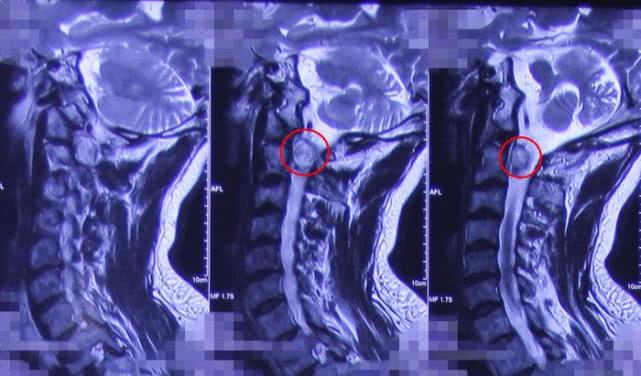

术前影像学资料

颈1-2

颈椎、胸椎MR平扫和增强显示,颈1-2、胸5-7水平椎管内髓外硬膜下可见,大小分别约为2.5cm*2.1cm*2.6cm、2.0cm*2.0cm*4.5cm的肿瘤物,贾主任最终诊断周叔颈1-2椎管内占位性病变,考虑是脊膜瘤,胸5-7椎管内占位病变,考虑是室管膜瘤。